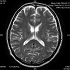

脊髄損傷を負い、後遺障害等級認定を受けるときに重要な役割を果たすのが、MRIなどの画像診断資料です。

骨傷性の脊髄損傷であれば比較的認識しやすいため、画像でしっかり診断できることが多いですが、中心性脊髄損傷の場合には撮影がなされずに見逃されてしまい、単なるむち打ちと診断されることがあります。

脊髄は円柱状なので、画像の角度や方法を変えることで画像所見が得られることがありますし、通常のMRIでの0.5テスラでは画像に写らない損傷箇所が、3テスラなら写るというケースもあるのです。

交通事故後早めの段階で検査を受け、精度の高いMRI画像を撮影、診断してもらうことが大切です。